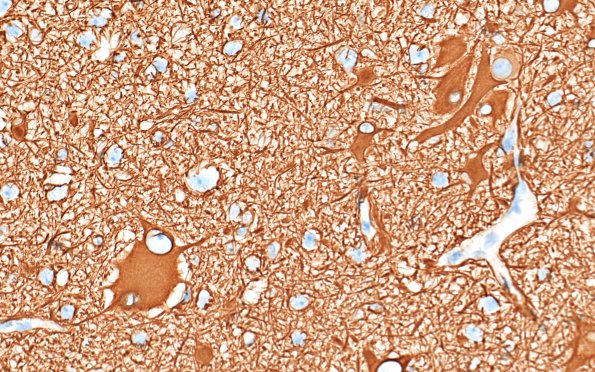

Washington University Experience | DEVELOPMENTAL MALFORMATIONS | Tuberous Sclerosis | 16C3 Tuber (Case 16) GFAP 40X

These dysmorphic ballooned, occasionally binucleate, cells are strongly immunoreactive in a context of small astrocytes and numerous astrocytic processes. (GFAP IHC)